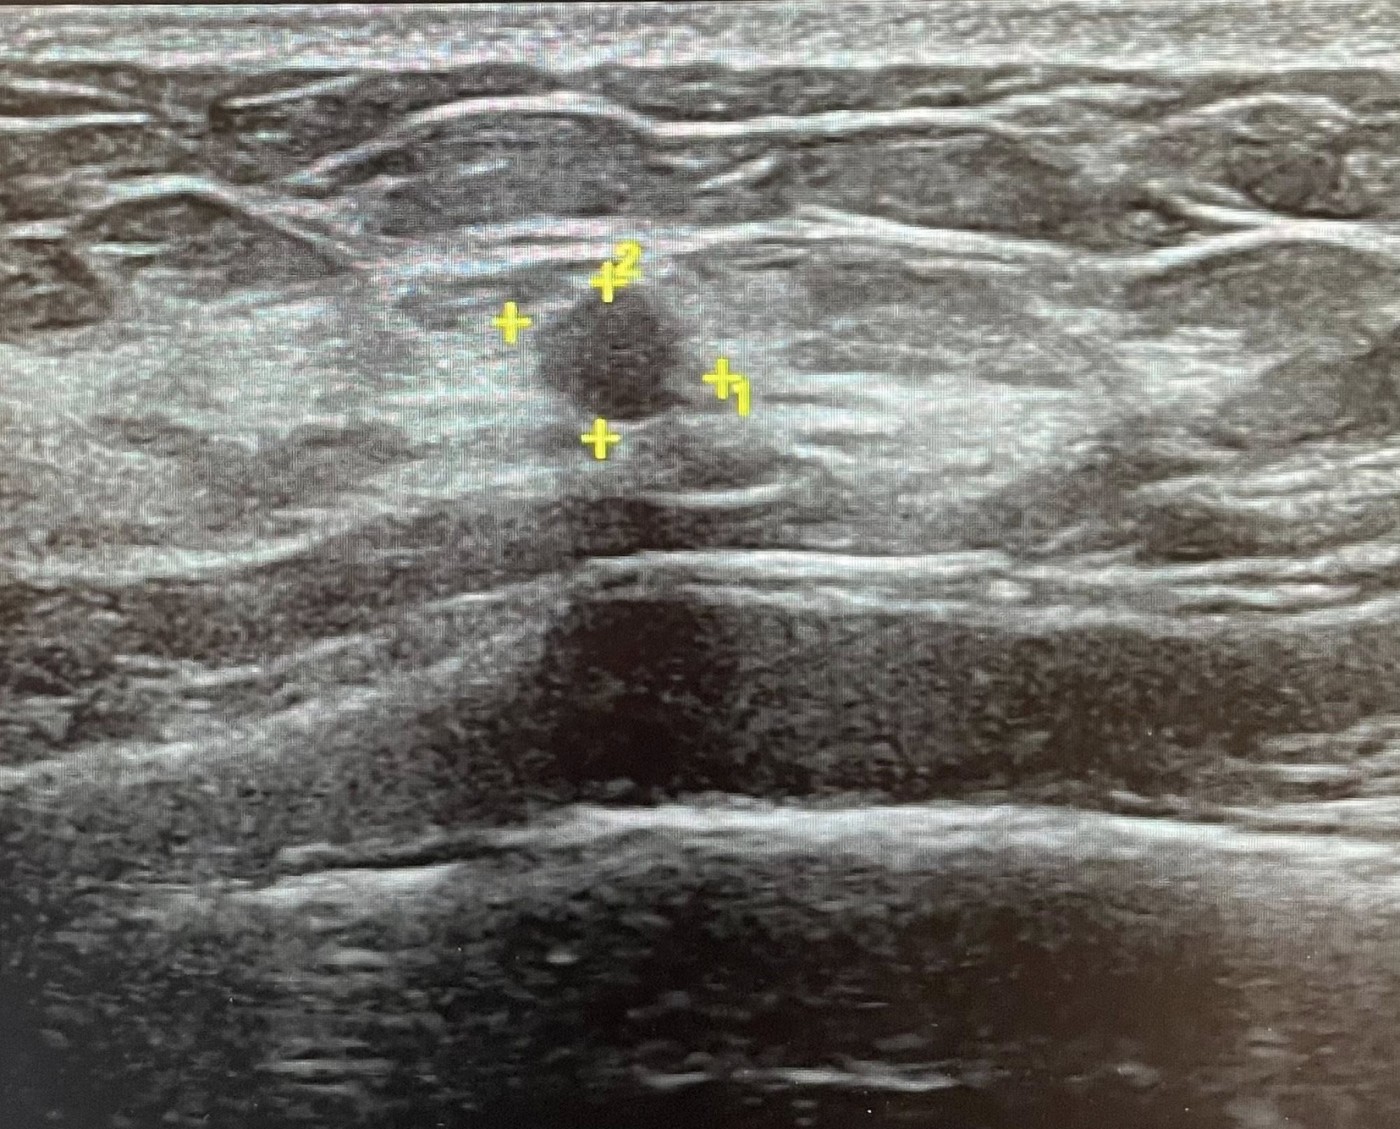

這位患者半年前在外院做乳房超音波,發現一顆 0.3 公分的小腫瘤。

半年後她轉到我門診追蹤,我重新檢視影像後,立刻注意到幾個變化:

大小幾乎沒變,但…

外觀卻「明顯不同」

- 形狀變得較不規則

- 結構出現非典型特徵

- 最關鍵的是:高大於寬(taller-than-wide)

當腫瘤的生長方向、形狀開始改變,就是需要切片確認的時機。

這位患者雖然腫瘤只有 0.3 公分,但外觀已經出現明顯變化。